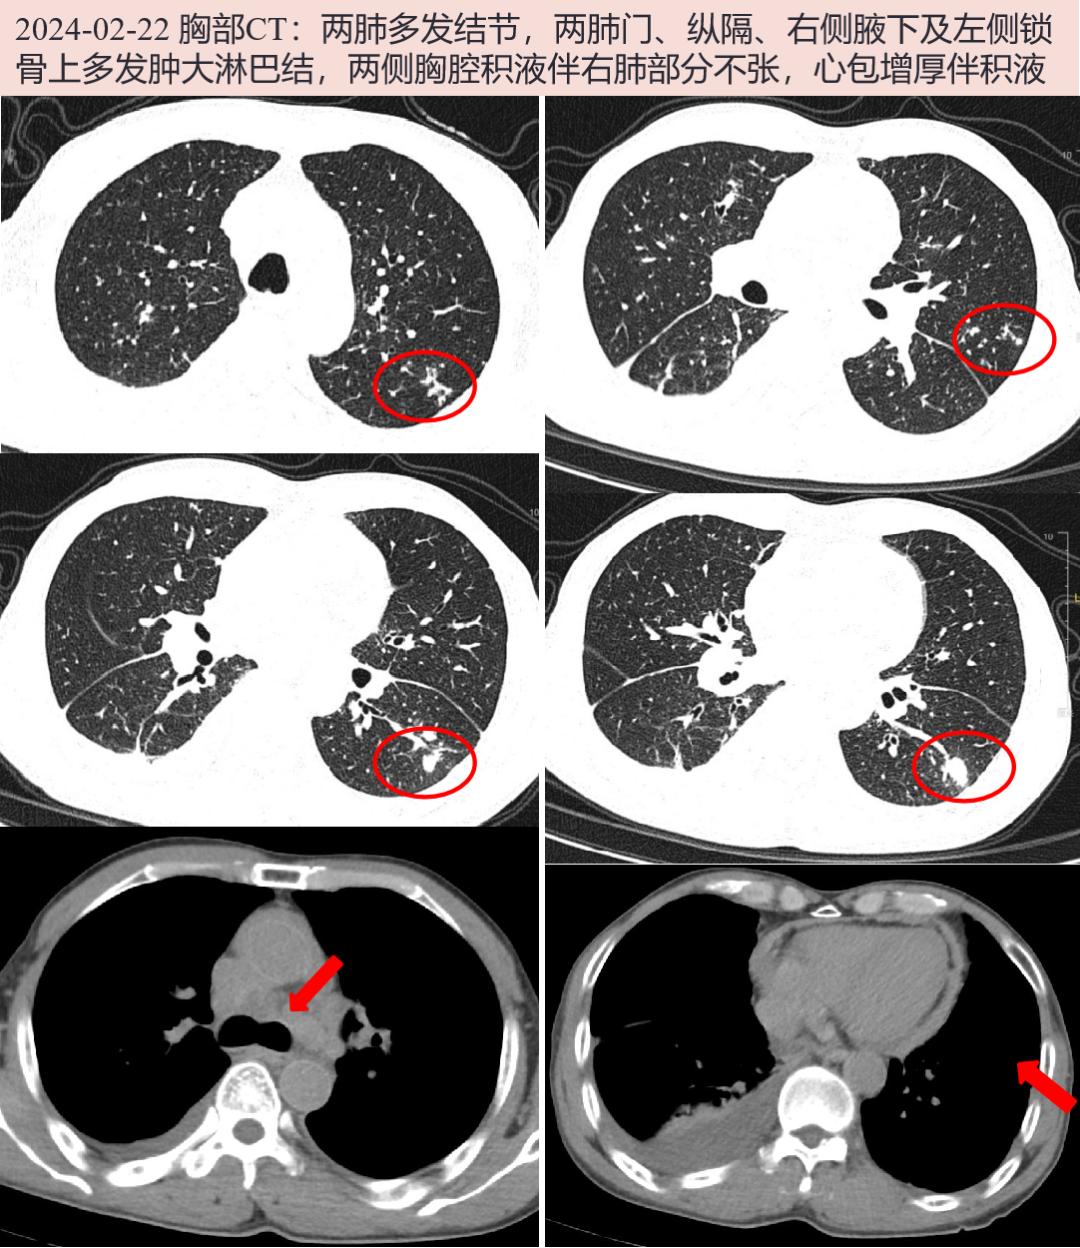

2024-02-22 胸部CT:两肺多发结节,两肺门、纵隔、右侧腋下及左侧锁骨上多发肿大淋巴结,两侧胸腔积液伴右肺部分不张,心包增厚伴积液。腹盆CT增强:肝小囊肿,双肾小囊肿;脾脏多发小低密度灶,脉管瘤可能;前列腺增生伴钙化;盆腔少量积液。

结核病:两肺多发结节,部分呈典型“树芽征”表现,伴胸腔及心包积液,锁骨上、纵隔多发淋巴结肿大;T-SPOT.TB阳性;胸水为渗出液,首先考虑结核病累及肺、淋巴结、胸膜心包可能。但患者无低热、盗汗、消瘦等毒性症状,胸水ADA不高,且成人锁骨上淋巴结结核少见,入院后可行肺活检或气管镜及EBUS-TBNA明确病灶性质,活检标本行涂片找抗酸杆菌、XPERT.TB、mNGS、分枝杆菌培养等寻找结核病原学依据。

肺癌:中老年男性,两肺多发病灶,最大者位于左下肺,呈结节状,似有分叶、毛刺,伴锁骨上及纵隔多发淋巴结肿大;虽血清及胸水肿瘤标志物阴性,胸水脱落细胞未见肿瘤性细胞;仍需警惕肺癌伴肺、淋巴结转移,可行左下肺结节穿刺活检以明确病理。

该患者T-SPOT阳性(抗原A/B 37/52),胸部CT检查两肺多发结节,部分有典型“树芽征”改变,多发淋巴结肿大、心包及胸腔积液。临床考虑结核病累及肺、淋巴结、胸膜及心包可能,也诊断性应用了抗结核治疗。但患者无结核毒血症状,胸水ADA不高,左下肺结节呈团块状,似有毛刺、分叶,如果漏诊肺癌仅当成肺结核进行治疗,则错过了肺癌的最佳治疗时机。因此行左下肺病灶穿刺,明确为低分化鳞癌。

在临床工作中,我们也要警惕陷入“一元论”的思维,因病理确诊而单一诊断为某一疾病,认为肺部多发结节及远处淋巴结肿大为转移灶,忽略了合并有其他疾病的可能。仔细阅CT片,该患者肺部其他病灶更倾向肺结核表现,T-SPOT阳性,且患者PET/CT检查见肺门、纵隔、腋窝、锁骨上淋巴结明显高代谢的均位于右侧,不符合左下肺癌常见转移部位,因此针对右侧锁骨上淋巴结进行了穿刺活检,病理提示肉芽肿性变,抗酸染色可疑阳性,XPERT.TB弱阳性,考虑淋巴结结核诊断明确,也间接支持其他淋巴结为结核可能。